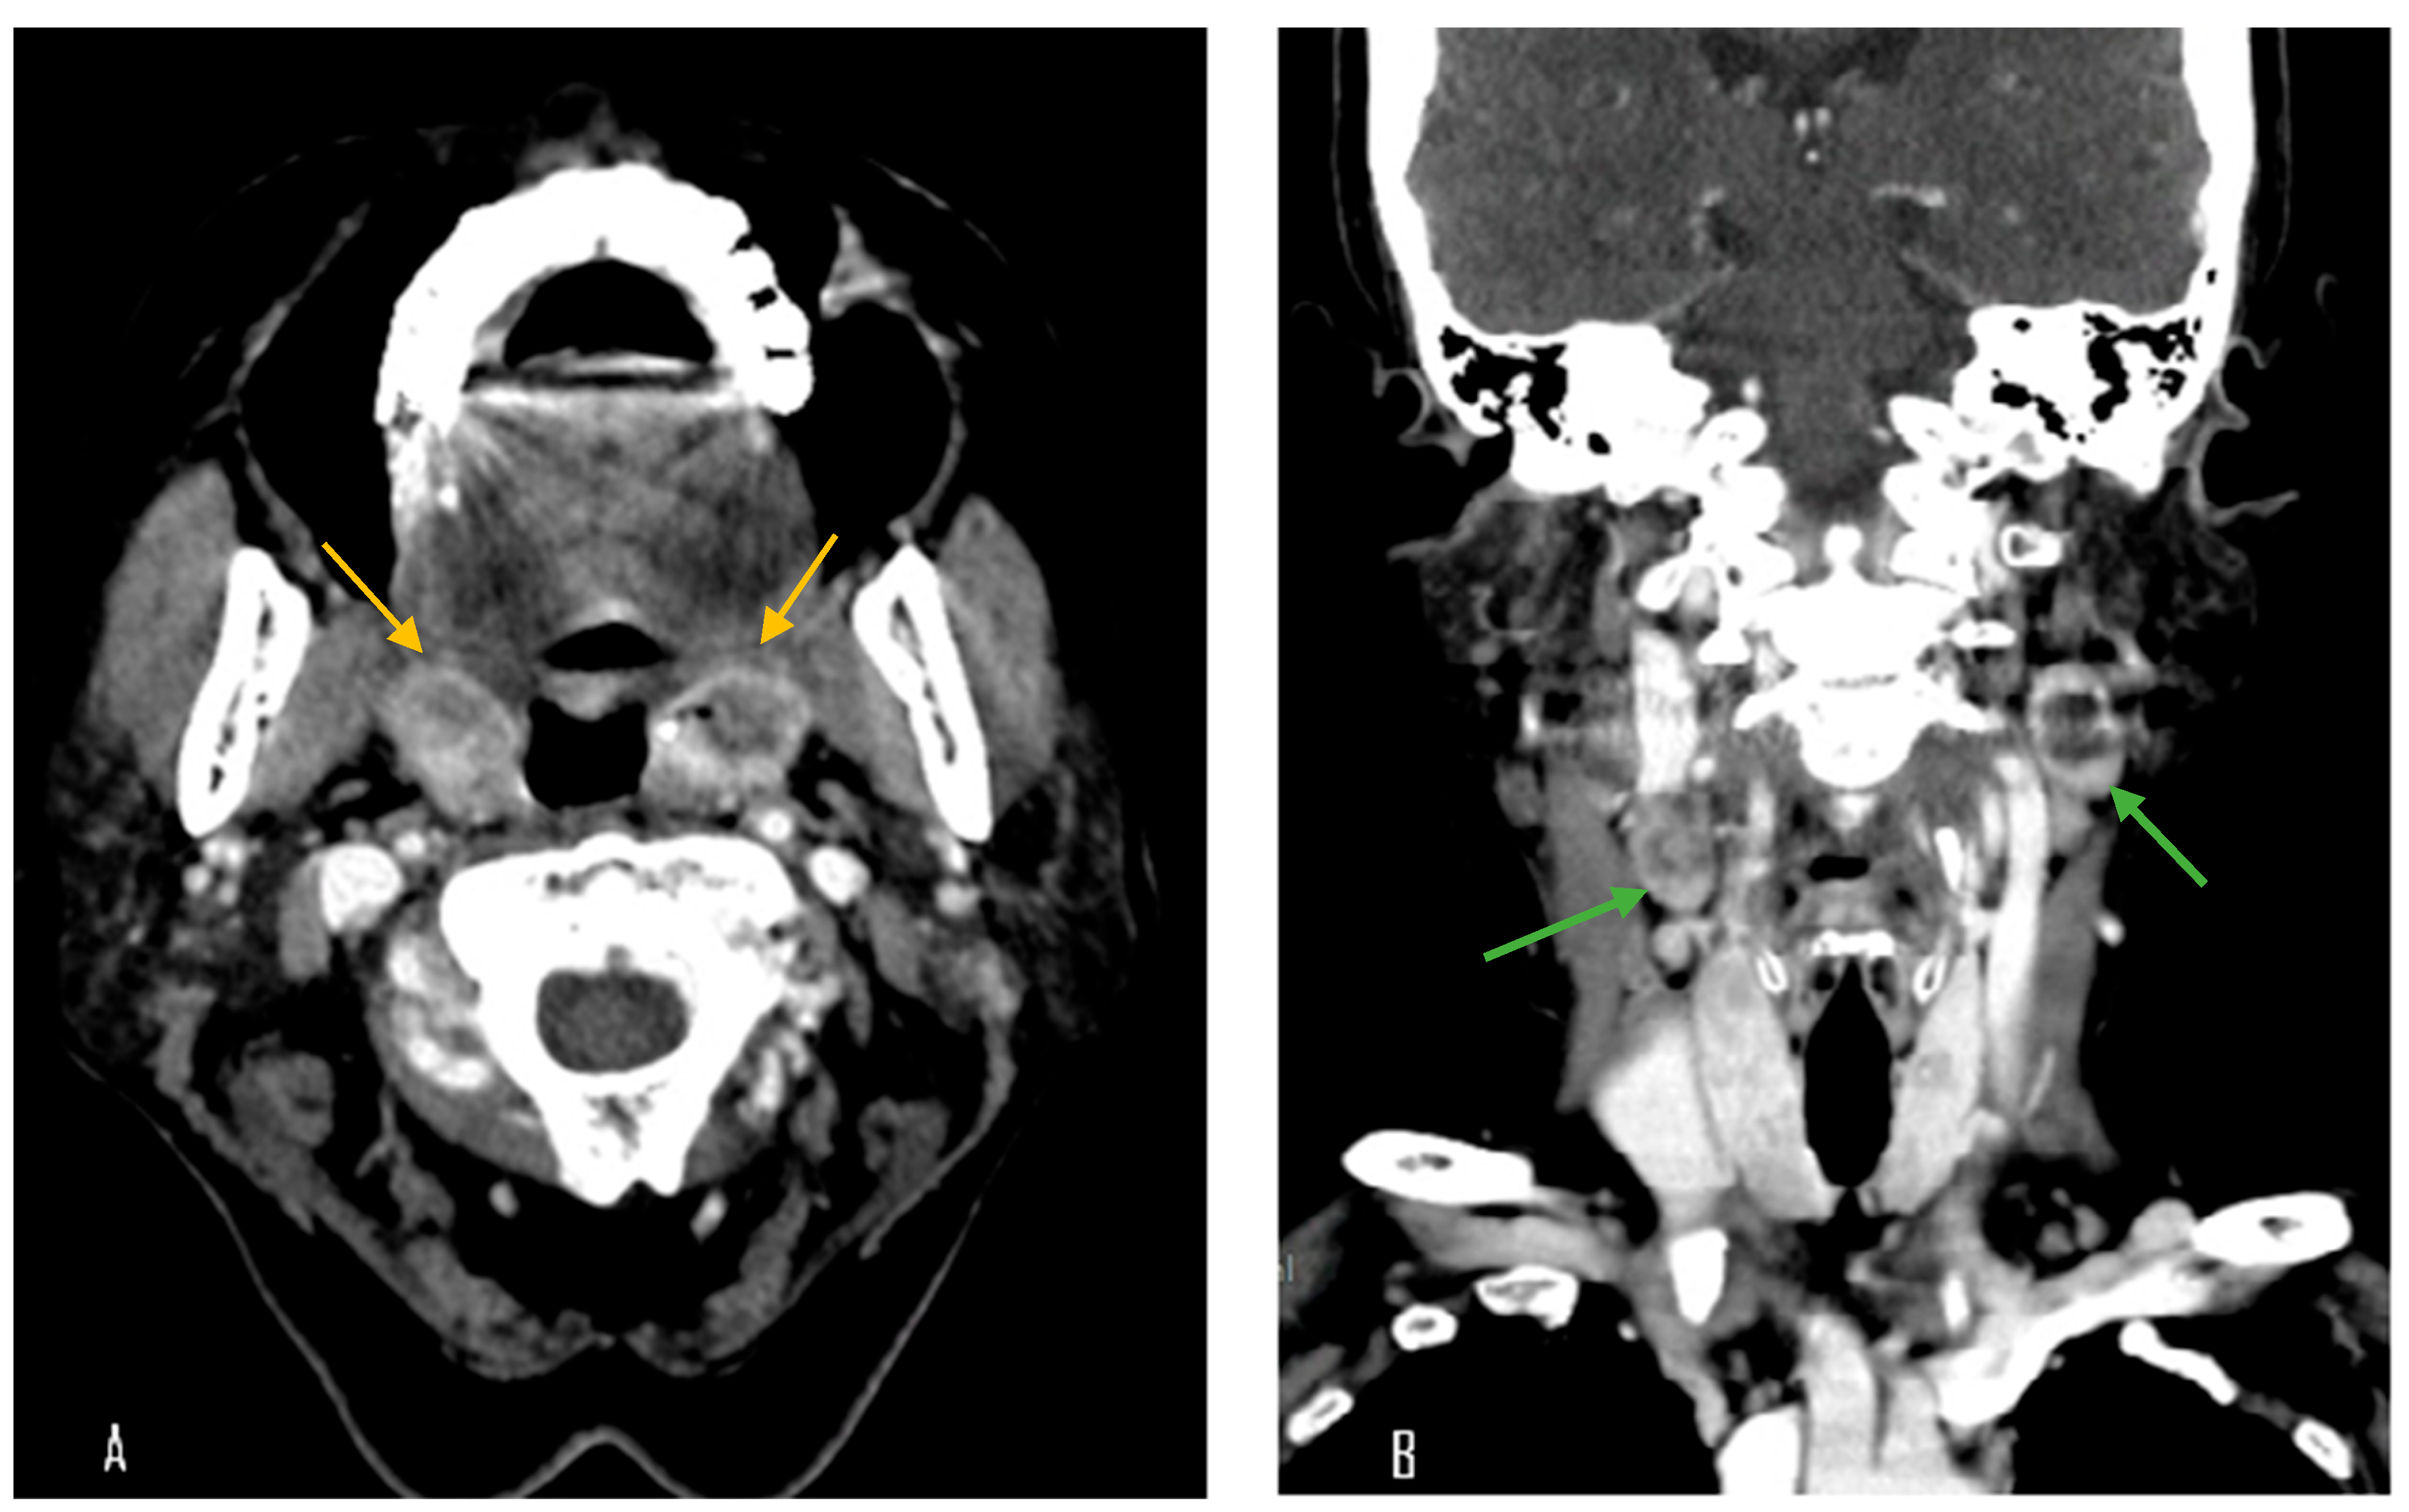

A 70-year-old female with a longstanding history of seropositive RA presented with recurrent episodes of sore throat for two months. Her medications included celecoxib, methotrexate sodium, hydroxychloroquine sulfate, and sulfasalazine. A physical examination in the outpatient clinic revealed erythematous swelling with purulent exudate over the bilateral palatine tonsils. Laboratory evaluation revealed a white blood cell count of 7000/μL, which falls within the normal reference range (approximately 4000–10,000/μL). The erythrocyte sedimentation rate was elevated at 30 mm/h (normal: 0–20 mm/h), and the C-reactive protein level was also increased at 14.95 mg/L (normal: <5 mg/L), indicating the presence of systemic inflammation. Contrast-enhanced computed tomography (CT) of the neck and chest revealed bilateral palatine tonsils with necrosis (Figure 1). Additionally, multiple necrotic lymphadenopathies were identified in the cervical region, superior mediastinum, and both axillary areas. Due to concern for underlying malignancy or infectious complications, the patient underwent bilateral tonsillectomy. Histopathological examination revealed features consistent with an EBV-positive lymphoproliferative disorder, polymorphic Hodgkin-like type, compatible with the diagnosis of an iatrogenic immunodeficiency-associated LPD (Figure 2). However, the tonsillar wound persisted with ulceration and necrosis more than one month after surgery, prompting further evaluation and clinical concern. Methotrexate was discontinued and the patient was managed conservatively with close monitoring. Subsequent follow-up showed clinical improvement, and no systemic chemotherapy was initiated (Figure 3).

Figure 1. Contrast-enhanced computed tomography (CT) images. (A) Axial view showing bilateral palatine tonsillar necrosis (yellow arrow). (B) Coronal view revealing multiple necrotic lymphadenopathies in the cervical region (green arrow).